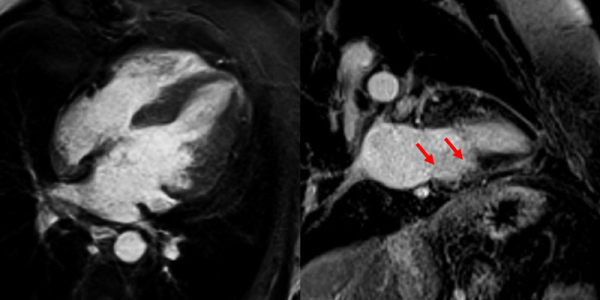

Conclusion

Au total, on retrouve la séquelle inféro-latérale déjà existante en 2011, et une ischémie limitée de 2-3 segments sur 17 en antéro-basal et antérolatéral.

L’ischémie est donc probablement en rapport avec la subocclusion de l’IVA proximale donnant les premières branches septales et la 2e diagonale, et non à cet ostium de mammaire interne gauche.

En effet, en cas de sténose significative au niveau de cet ostium, nous retrouverions une large ischémie dans tous les territoires, antéro-septo-apical, latéral et inférieur.

Devant l’ischémie limitée à l’IRM de stress et après discussion pluridisciplinaire de l’équipe de Cardiologie de Lariboisière, il a été décidé d’optimiser le traitement médical en majorant le traitement anti-ischémique (majoration de son traitement par bétabloquant et introduction d’un inhibiteur calcique et de dérivés nitrés per os).